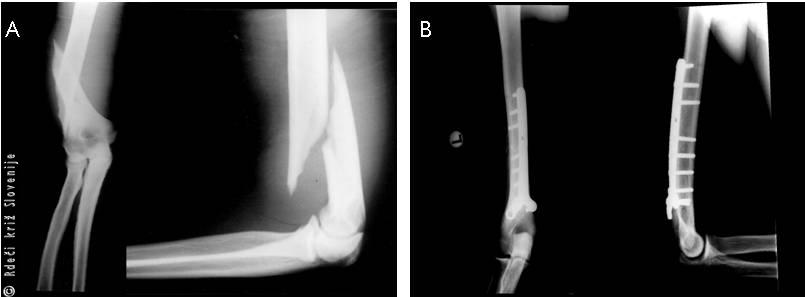

Primer 1

24-letni moški na služenju vojaškega roka je bil v urgentno ambulanto prepeljan po tekmi v polaganju rok med prijatelji. V želji po zmagi je v trenutku, ko je strl upor nasprotnika, zaslišal pok in začutil bolečino v zgornjem udu. Dve uri zatem je občutil hudo bolečino v predelu nadlahtnice in komolca. Gibanje v komolcu je bilo omejeno in boleče. Pri pregledu je bila vidna oteklina v spodnjem delu nadlakti, spremenjena oblika in močna bolečina ob pritisku na poškodovani predel. Gibanje v komolcu je bilo zavrto. Ni bilo znakov za poškodbo žil ali živcev. Rentgenska slika v dveh projekcijah je pokazala zlom spodnjega dela nadlahtnice s premikom odlomkov. Potrebna je bila odprta naravnava in učvrstitev zloma.

Slika 7

Na rentgenski sliki je viden zlom nadlahti v spodnjem delu s premikom, pred (A) ter po odprti naravnavi in učvrstitvi s ploščo in vijaki (B).